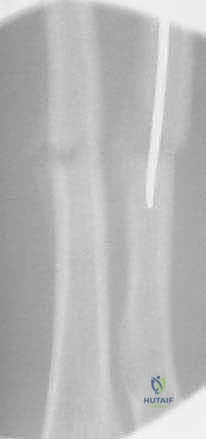

3. فتح المداخل الجراحية (Incision)

يتميز الدكتور هطيف بإجراء شقوق جراحية تجميلية دقيقة لا تتجاوز 2 سم:

* لعظم الكعبرة: يتم عمل شق صغير بالقرب من الرسغ (فوق الكردوس البعيد للكعبرة) مع حماية فائقة للفرع الحسي للعصب الكعبري.

* لعظم الزند: يتم عمل شق صغير بالقرب من الكوع (تحت الناتئ الزجي).

4. فتح القناة النخاعية

باستخدام أداة دقيقة (Awl)، يقوم الدكتور هطيف باختراق قشرة العظم لإنشاء نقطة دخول للمسمار، مع الحرص الشديد على عدم إيذاء صفيحة النمو القريبة.

5. إدخال المسمار المرن

يتم إدخال المسمار المرن (المثني مسبقاً)